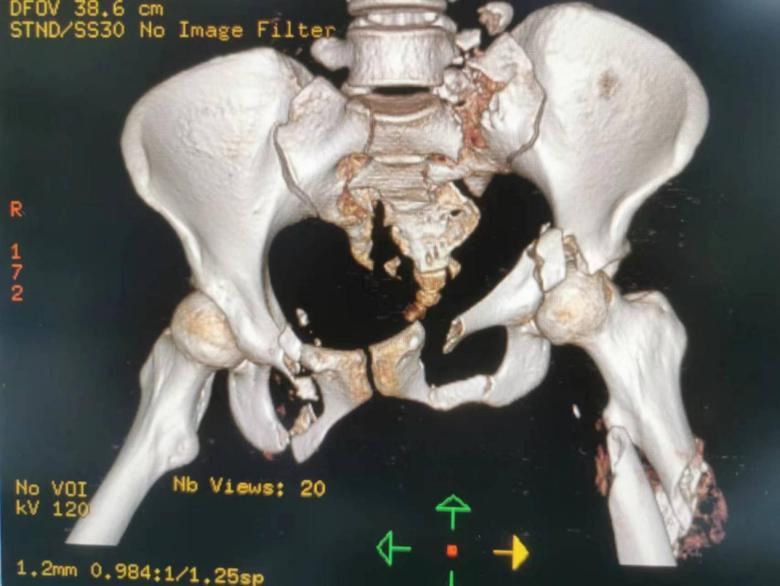

20 岁的患者小高(化名)从高处坠落伤致全身多处骨折,还合并张力性气胸、失血性休克、急性呼吸窘迫综合征等,入院后被送入 ICU 抢救。

小高稳定生命指征后转入骨科进行手术治疗,但光是需要手术的骨折就有 5 处之多!

小高转入骨科时更是错过了手术的最佳时机:骨盆粉碎性骨折已经变成了陈旧性,正常解剖结构改变、骨折碎裂的复位使手术变得困难重重;她身上还有多种并发症,也增加了不少难度。

考虑到小高才 20 岁,不做手术的话将终身卧床,萨米医疗骨科团队立即组织了全科室讨论,并为小高制定了详尽的手术方案——骨盆骨折切开复位内固定术,手术由丁斌主任主刀。

「这类骨折最大特点是复合损伤多,常危及生命,伤残率高。骨盆内解剖结构及周边关系复杂,具有丰富的血管、复杂的神经走形解剖特点而且骨盆解剖形态还不规则……」

「因此骨盆骨折手术难度大、手术风险高,骨盆骨折内固定术一直是骨科领域最复杂、最具挑战性的手术之一。但我们有丰富的经验和充足的准备,有信心可以做好它。」萨米医疗骨科丁斌主任如此说道。

最后在丁斌主任及骨科团队的齐心协力下,小高的复杂陈旧性骨盆骨折手术顺利完成!